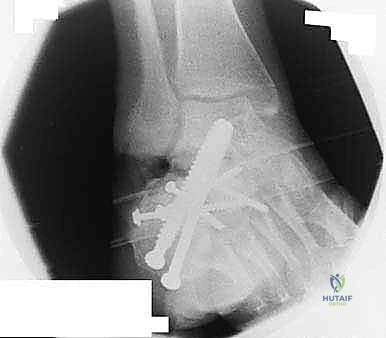

2. التصوير بالأشعة السينية (X-rays) مع تحمل الوزن

صور الأشعة السينية هي الخطوة الأولى. يطلب د. هطيف صوراً بوضعيات محددة (أمامية خلفية، جانبية، ومحورية Harris view) لتقييم:

* زاوية بوهلر (Böhler's angle) وزاوية جيسان (Gissane's angle) لتقييم فقدان الارتفاع والانخساف.

* مدى اتساع الجدار الجانبي.

* علامات التهاب المفاصل (تضيق المسافة المفصلية، تكون نتوءات عظمية، وتصلب العظم تحت الغضروف).

3. التصوير المقطعي المحوسب (CT Scan) مع إعادة البناء ثلاثي الأبعاد (3D Reconstruction)

لا يمكن التخطيط لجراحة تصحيح سوء التئام عظم العقب بدون أشعة مقطعية. توفر الأشعة المقطعية رؤية دقيقة للتشريح العظمي المشوه، وتحدد بدقة مكان الانحشار الشظوي، حالة الأسطح المفصلية، ومسار الأوتار. التخطيط ثلاثي الأبعاد يسمح للجراح ببناء نموذج افتراضي للقدم وتحديد أماكن القطع العظمي المطلوبة بدقة مليمترية قبل الدخول إلى غرفة العمليات.